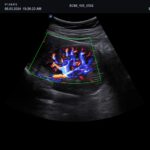

| Software Disponibles OB/GIN: | 3D/4D convexo y endocavitario, Live HQ, Volume Advance, Auto Translucencia Nucal (NT), X+ Auto Biometry, X+ Follicle, Silhouette View |